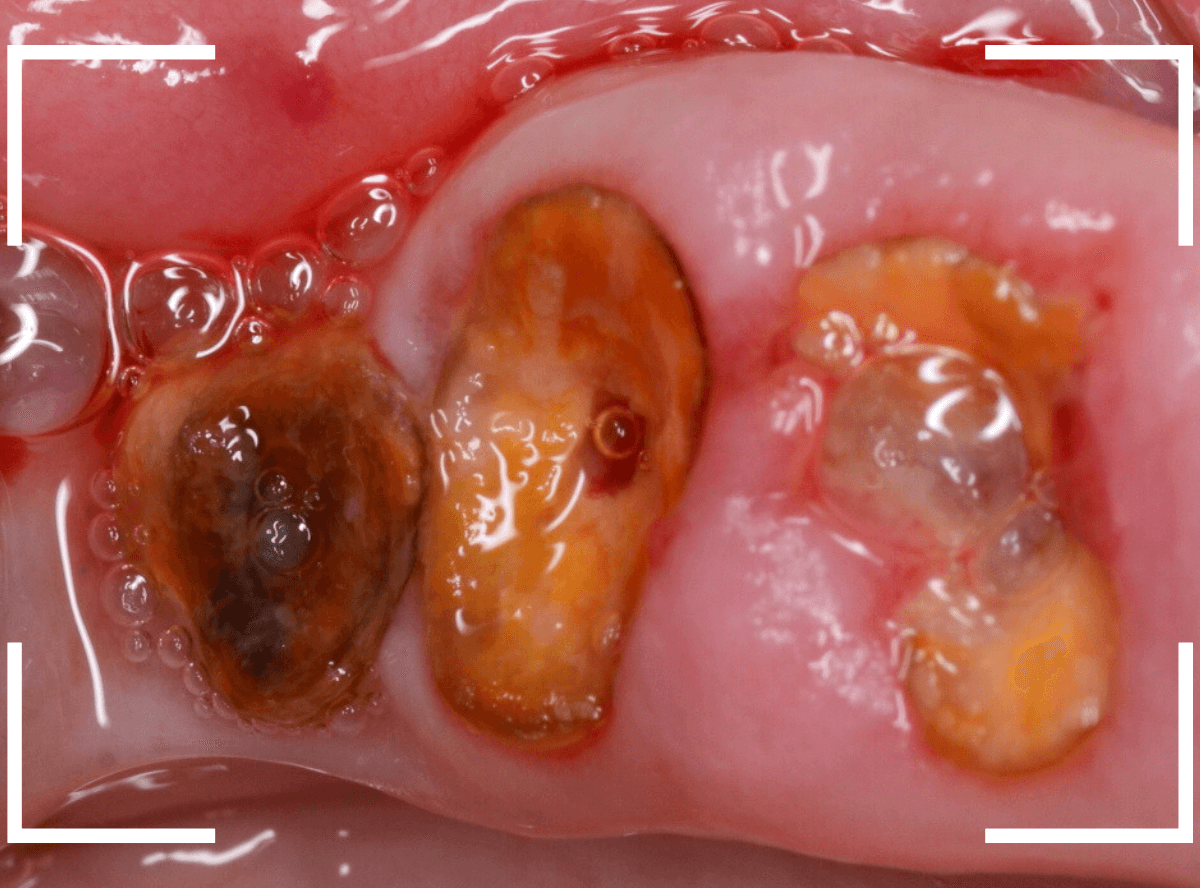

今回は、痛みもなく、見た目にはまだ治療で何とかなりそうに見えるケースです。

大きな虫歯なのはわかりますが、治療で何とかなりそうにも見えます。

しかし、レントゲン写真で確認すると、実際には虫歯でボロボロで、歯の根っこだけの状態なのがわかります。

残念ながら抜歯が必要ですが、抜歯も難しくなる可能性が高いケースです。

予想通り、処置時に歯がバラバラになってしまい、時間がかかってしまいましたが、何とか抜歯を終わらせました。

虫歯の状態は見た目や症状だけではわかりません。

くれぐれも自己判断で放置することは避けてくださいね。